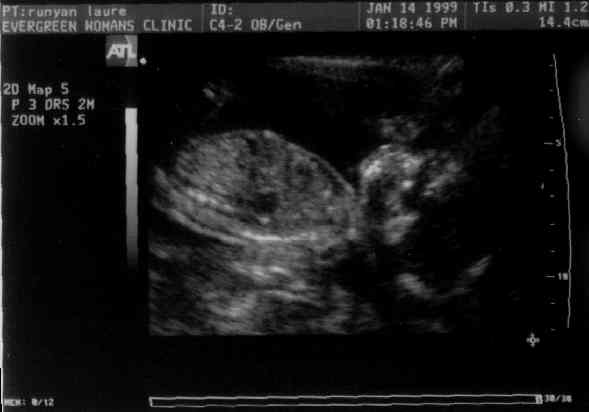

Baby Profile - Uh Oh! Too much Zandonella influence!